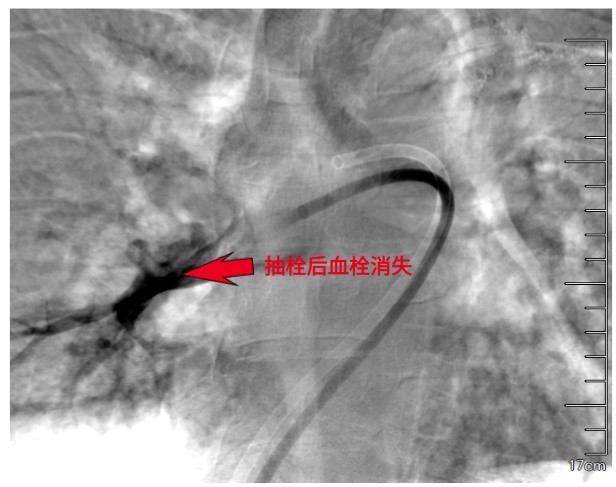

医生将一种专用的大腔血栓抽吸导管沿导丝送至血栓内部。随着负压的启动,血栓被源源不断地吸入体外收集装置。术后即刻的肺动脉造影显示,先前中断的血流通道被重新打通,右心压力随之下降。这场在血管内部进行的“疏通作业”,安静而高效,没有开胸的惊心动魄,却完成了同样关键的使命。

精准靶向,直击病灶:在数字减影血管造影(DSA)的实时高清引导下,介入导管可被精确导航至肺动脉内的血栓部位,实现“指哪打哪”的精准治疗。通过专用的抽吸导管,可像“微型吸尘器”一样,将堵塞主干的血栓快速吸出,术中即可恢复肺动脉主干血流,患者血压、血氧常在数分钟内得到改善。